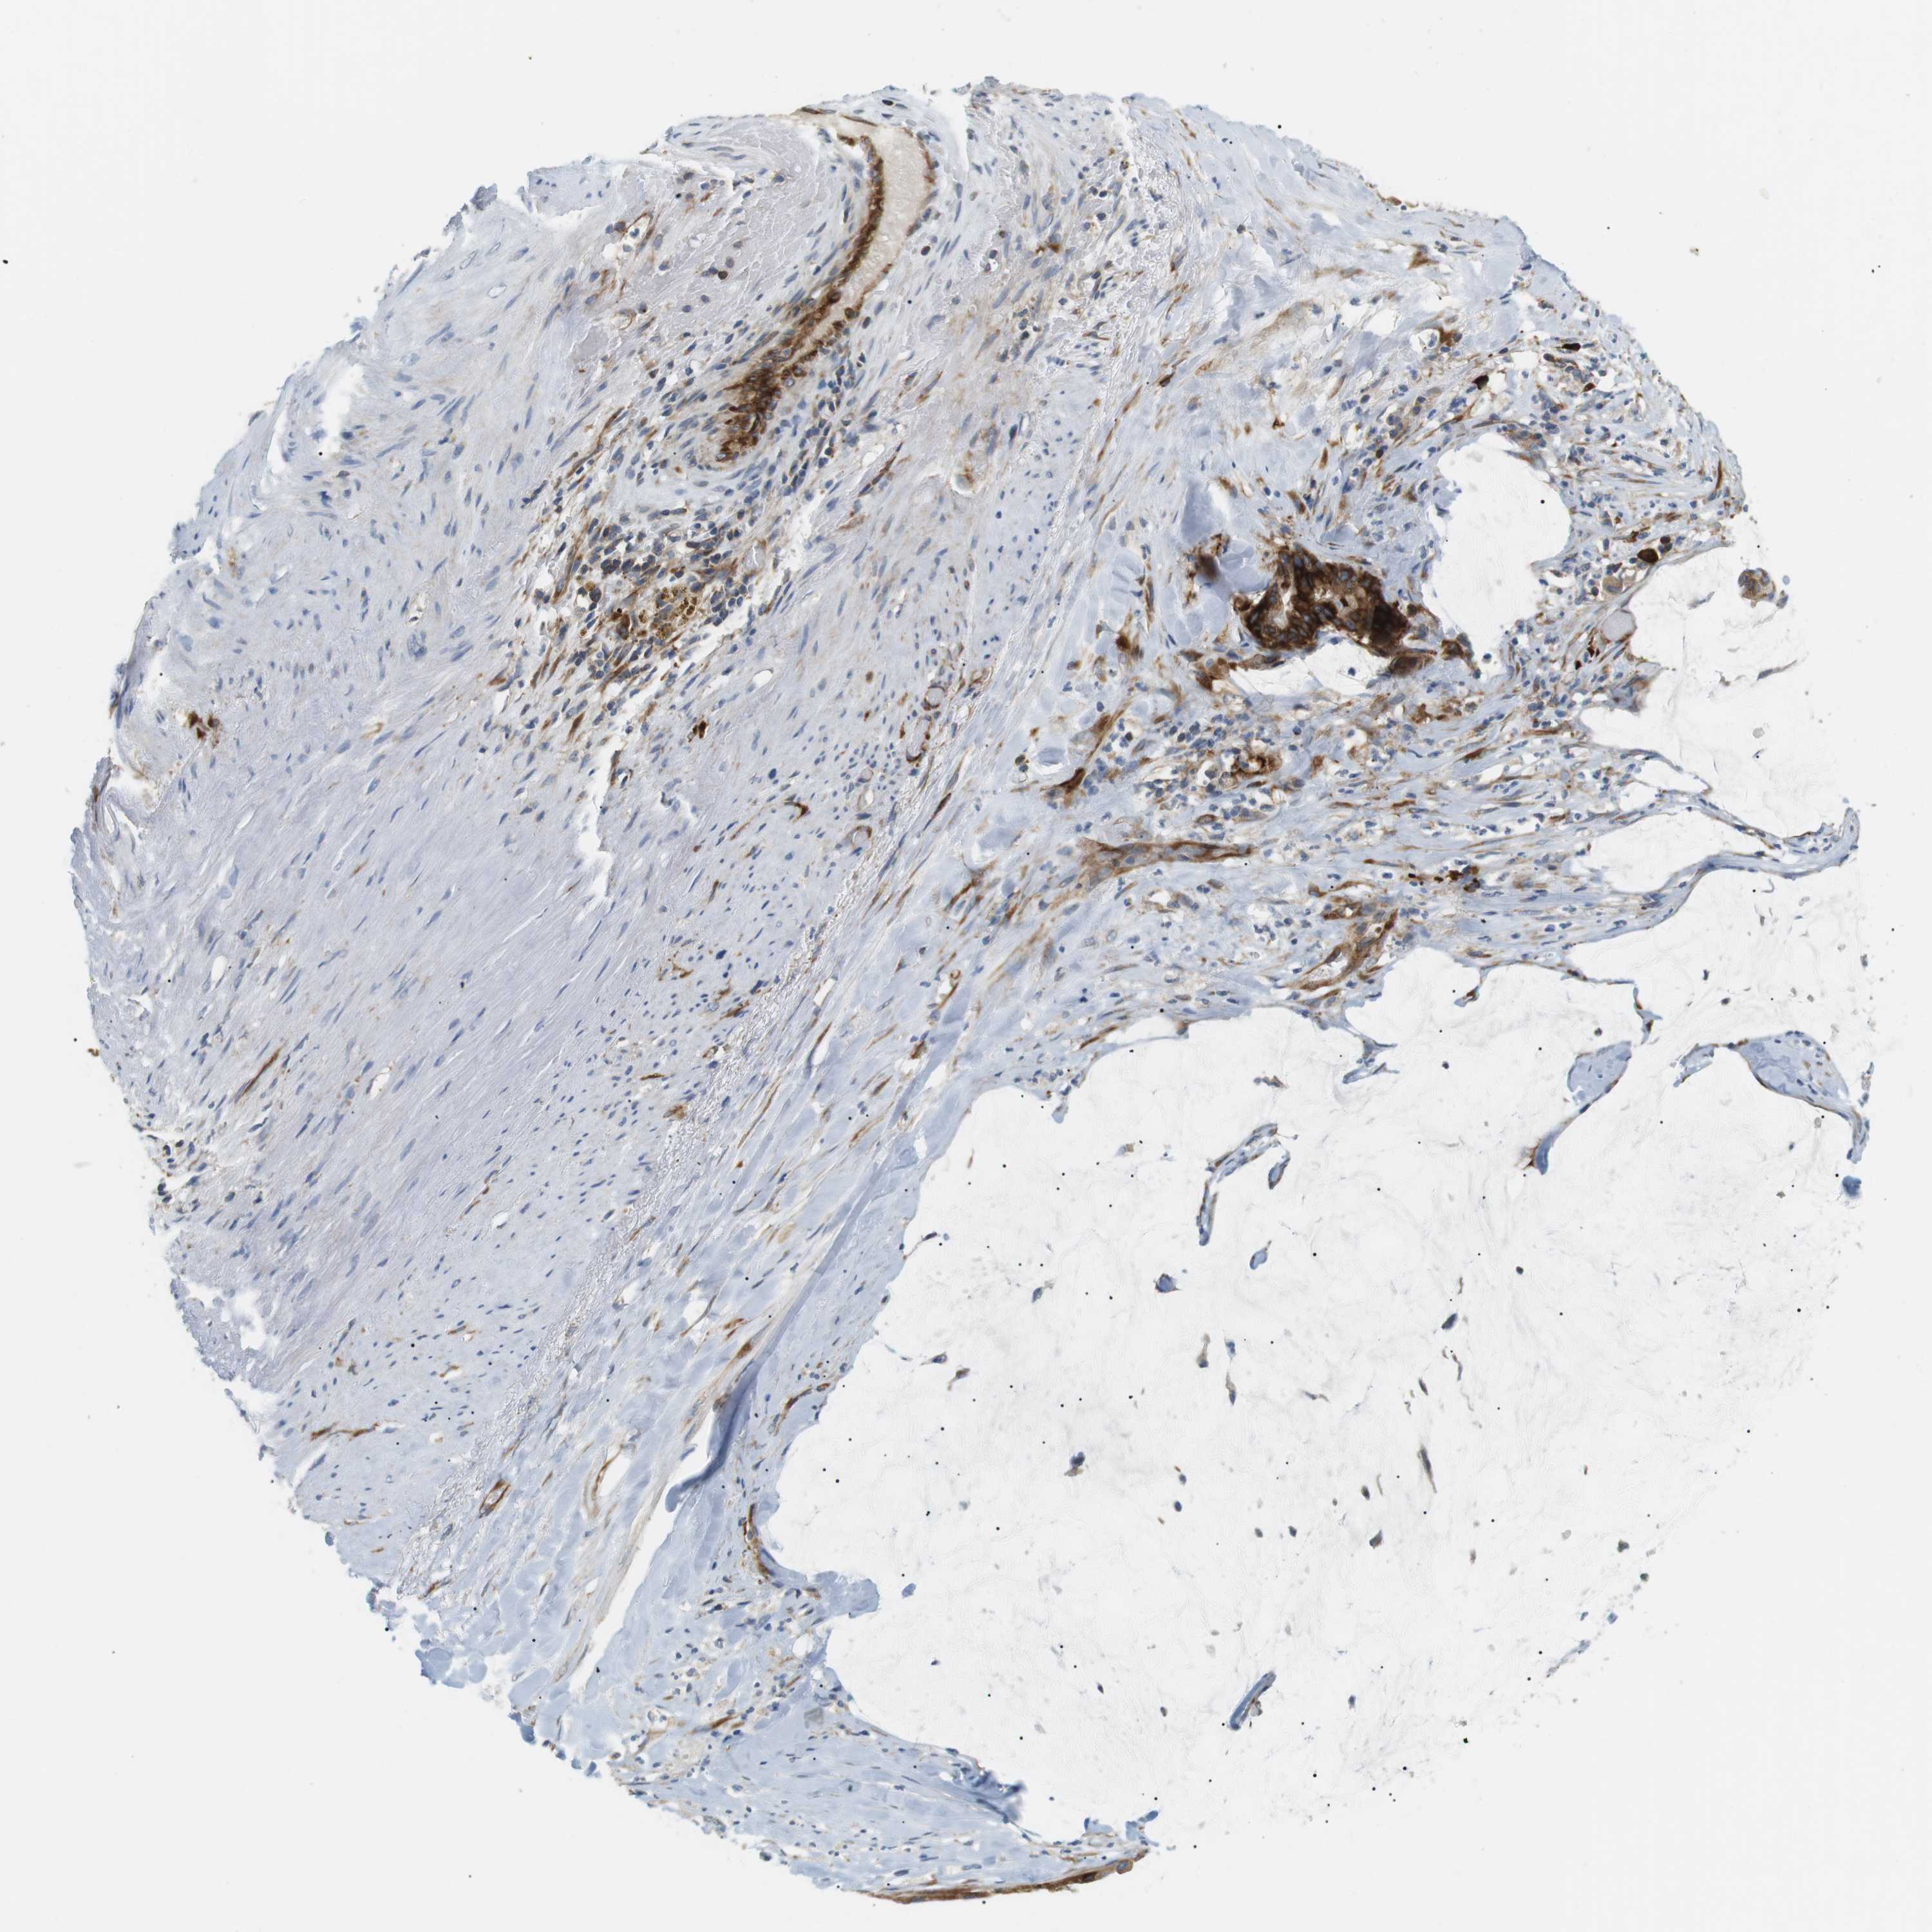

PANCREATIC CANCER - Protein expressioni

A mouse-over function shows sample information and annotation data. Click on an image to view it in a full screen mode. Samples can be filtered based on level of antibody staining by selecting one or several of the following categories: high, medium, low and not detected. The assay and annotation is described here.

Note that samples used for immunohistochemistry by the Human Protein Atlas do not correspond to samples in the TCGA dataset.

Antibody stainingi

Antibody staining in the annotated cell types in the current human tissue is reported as not detected, low, medium, or high, based on conventional immunohistochemistry profiling in selected tissues. This score is based on the combination of the staining intensity and fraction of stained cells.

Each image is clickable and will lead to virtual microscopy that enables deeper exploration of all samples and also displays staining intensity scores, fraction scores and subcellular localization as well as patient and tissue information for each sample.

Antibody HPA014396

Staining

High

Medium

Low

Not detected

Intensity

Strong

Moderate

Weak

Negative

Quantity

>75%

75%-25%

<25%

None

Location

Nuclear

Cytoplasmic/membranous

Cytoplasmic/membranous,nuclear

Adenocarcinoma, NOS